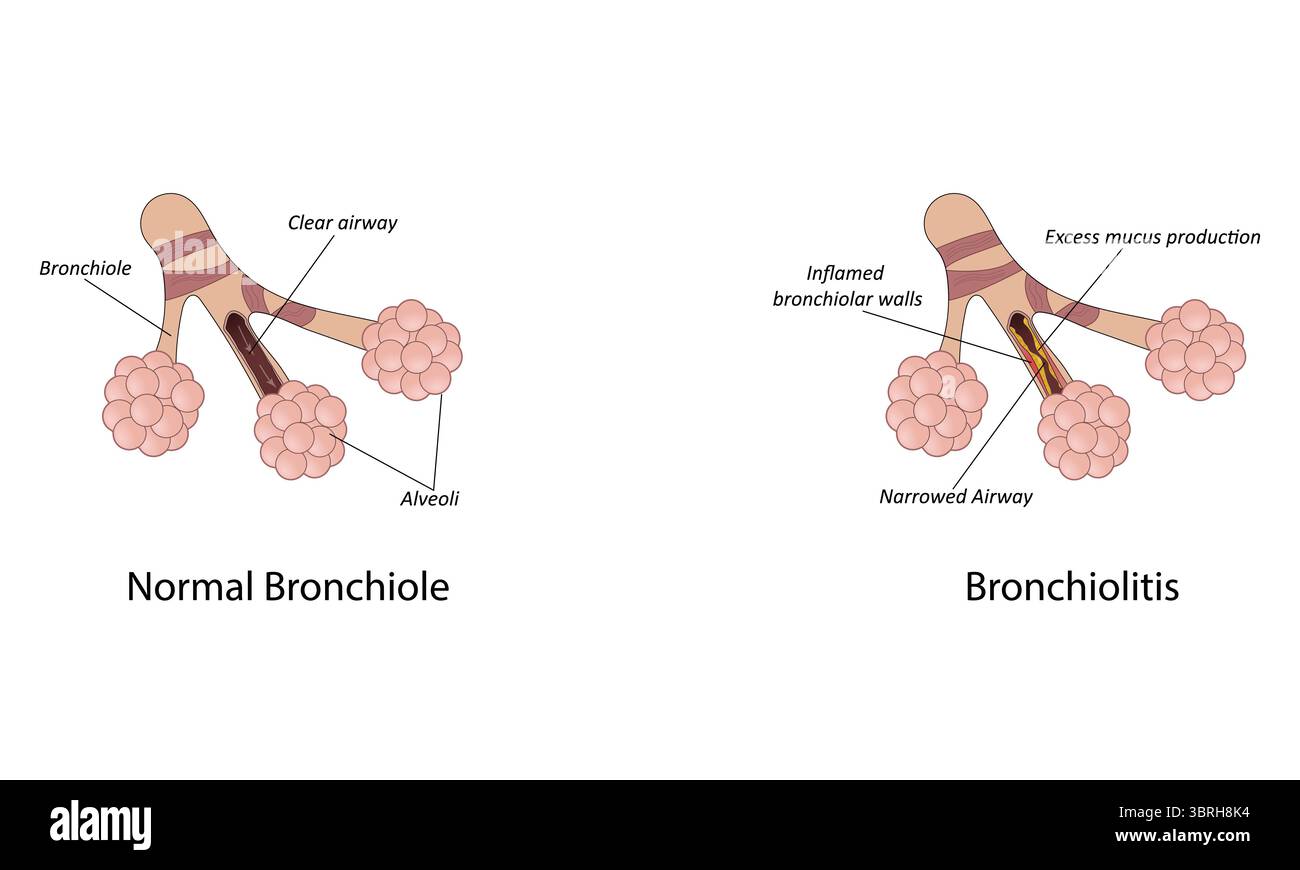

Bronchiolitis vector illustration Stock Vectorhttps://www.alamy.com/image-license-details/?v=1https://www.alamy.com/bronchiolitis-vector-illustration-image685721432.html

Bronchiolitis vector illustration Stock Vectorhttps://www.alamy.com/image-license-details/?v=1https://www.alamy.com/bronchiolitis-vector-illustration-image685721432.htmlRF3BRH8K4–Bronchiolitis vector illustration